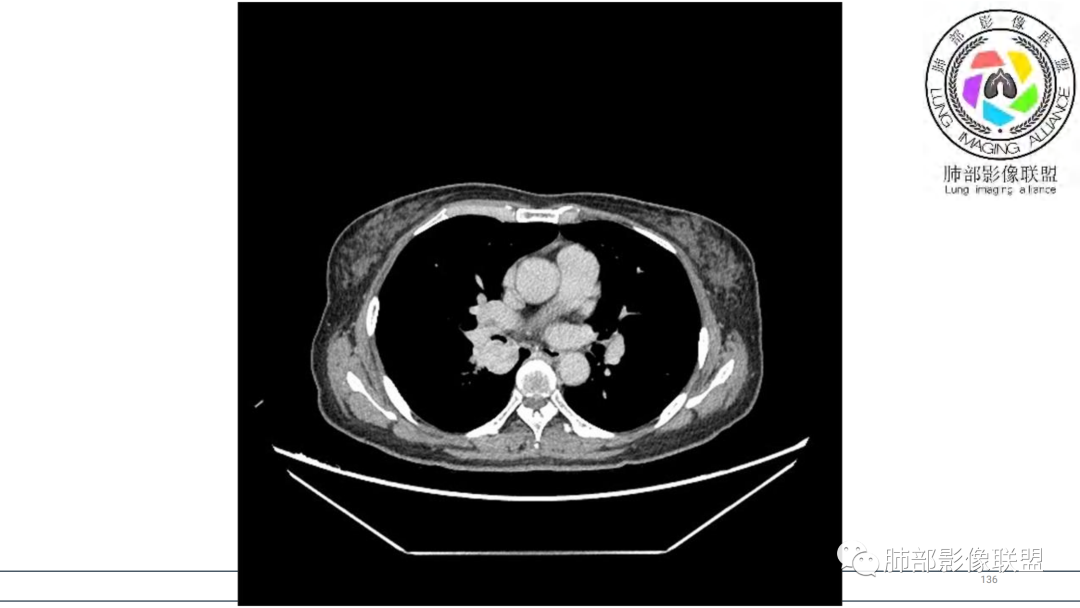

影像与临床:

1.因声带良性病变术前CT检查意外发现肺部肿块。

2.右肺下叶及中间段支气管后方类圆形块影,边界较清楚,未见分叶及毛刺,病灶部分突入支气管腔内(冰山一角),局部管腔狭窄,相应肺叶未见片影或体积变化。

3.块影密度均匀,未见液化坏死及钙化,渐进性强化,强化显著。

4.双肺门及纵隔未见增大淋巴结。未见胸腔积液。

综合分析:

中青年女性,支气管管腔内外肿块(“冰山征”),边界较清楚,强化显著,未见阻塞性肺不张,尽管未出现“类癌综合征”临床表现,仍然符合典型类癌影像学表现。